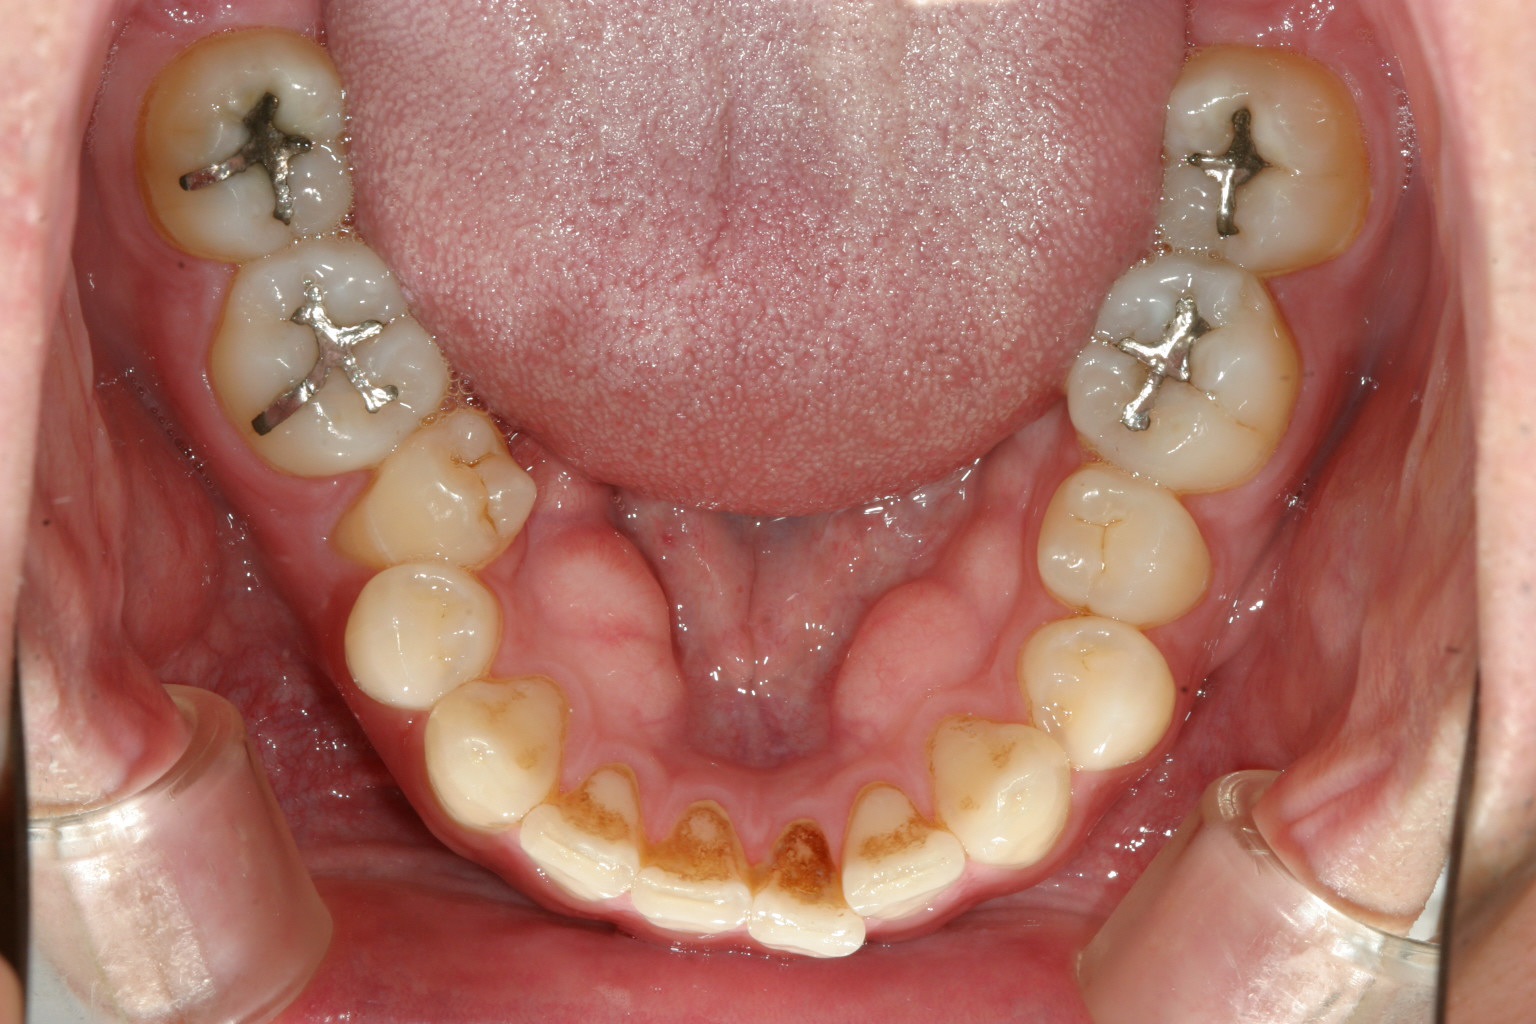

下顎には前歯に叢生が見られ小臼歯部が内方傾斜しています。

今回のケースは下顎の臼歯が内方に傾斜している為咬合高径が低くなり結果として

かみ合わせが深くなっていました。

こう言った場合まず上下顎のアーチを広げるとともに、下顎の臼歯の傾斜も立て直す事により咬合高径も上がり結果として叢生も取れ上下前歯のガタつきも改善しました。